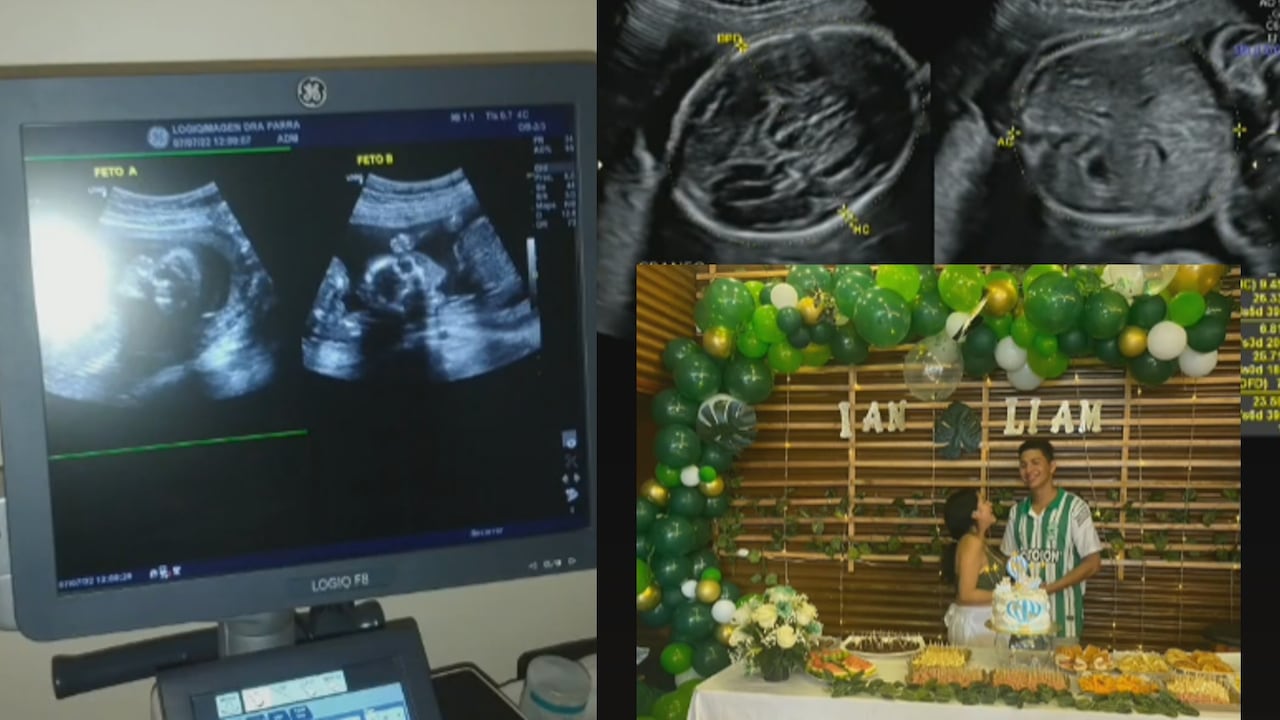

Un video que rápidamente se hizo viral cuenta la historia de una pareja que, durante los primeros siete meses de embarazo, estuvieron convencidos de que esperaban gemelos; incluso, organizaron un baby shower y ya tenían listos los nombres para los nuevos integrantes de la familia.

Durante los exámenes de rutina que le realizaron desde que se enteró de que estaba embarazada, siempre vio en las ecografías a sus dos pequeños, que se llamaría Ian y Liam.

Sin embargo, el último control que se realizó la dejó a ella y a su esposo sin palabras, pues resulta que un tercer hijo estaba en camino; así es, no eran gemelos, sino trillizos, y lo que sucedió, al parecer, es que el otro feto que se estaba creando siempre estuvo escondido detrás de los de sus hermanos.

“Cuando me dijeron son gemelos, no creía; ahora que sé que son 3 estoy en ‘shock’, pero muerta de amor”. “También me dijeron que podían ser mellizos y luego que son gemelos, pero no vieron al tercero”, “mi bebé ha sabido meterse mucho por mis costillas y nunca notaron que estaba ahí”, fueron algunas de las respuestas de la joven.

Según los videos posteriores a la publicación donde contó su sorpresa, sus bebés aún no nacen; mientras tanto, registra paso a paso cómo evoluciona su embarazo y crece su barriga.